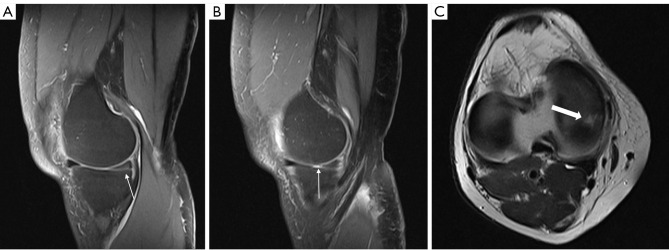

Abstract Image